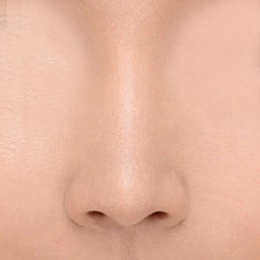

حالتی که فقط سوراخ های بینی رو به بالا است

اگر فقط سوراخ های بینی به سمت بالا باشد، نوک بینی با در نظر گرفتن زاویه نازولبیال پایین می آید و اصلاح می شود. این کمک می کند تا چهره کلی را به جلوه پیچیده ای تبدیل کنید.